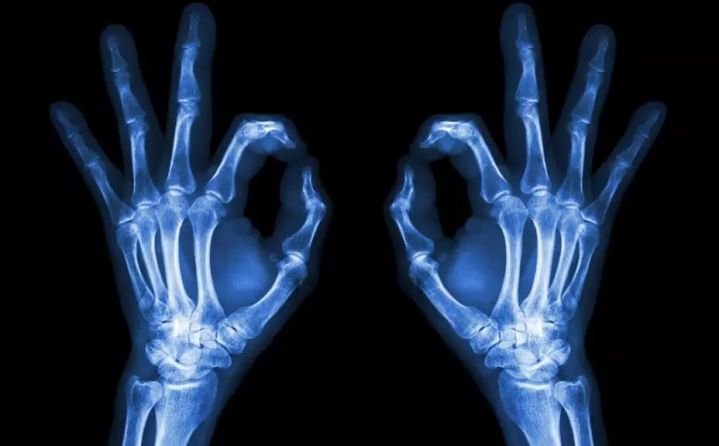

2、颈椎腰椎——最佳选核磁、次选CT

0.webp (4).jpg

颈椎病、腰椎间盘突出等椎间盘疾病需要观察椎间盘与相应的神经根,要想更好观察这些软组织,最优选择就是核磁。同样,对于关节、肌肉、脂肪组织检查,核磁也是首选。